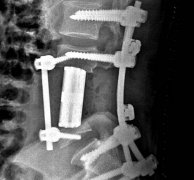

2017-03-15·3D打印换脊骨!南医三院开展全省首例3D打印人工椎体植入手术

手术中,在钉棒系统的固定下,医生为患者植入了人工椎体。 脊椎上长了一个大肿瘤需要连肿瘤带椎体整体切除,缺损的脊柱怎么办?用3D打印的人工椎体来置换! 近日,南方医科大学附属第三医院(广东省骨科医院)骨肿...

2017-03-15·广东首例用3D打印脊骨接上患肿瘤被切部位手术完成

近日,南方医科大学附属第三医院(广东省骨科医院)骨肿瘤科团队成功为一名脊索瘤患者切除了脊椎,并植入3D打印人工椎体,这是广东完成的首例3D打印换脊骨手术。 “该名患者的肿瘤长在血管丰富的下腰椎,也是神经分...

南方医科大学第三附属医院(广东省骨科医院)14日公布,成功为一名脊索瘤患者切除肿瘤,并植入3D打印人工椎体。这是广东省首例3D打印人工椎体植入手术。目前患者(中间)恢复良好,已下地行走,当天向医生送上锦旗...